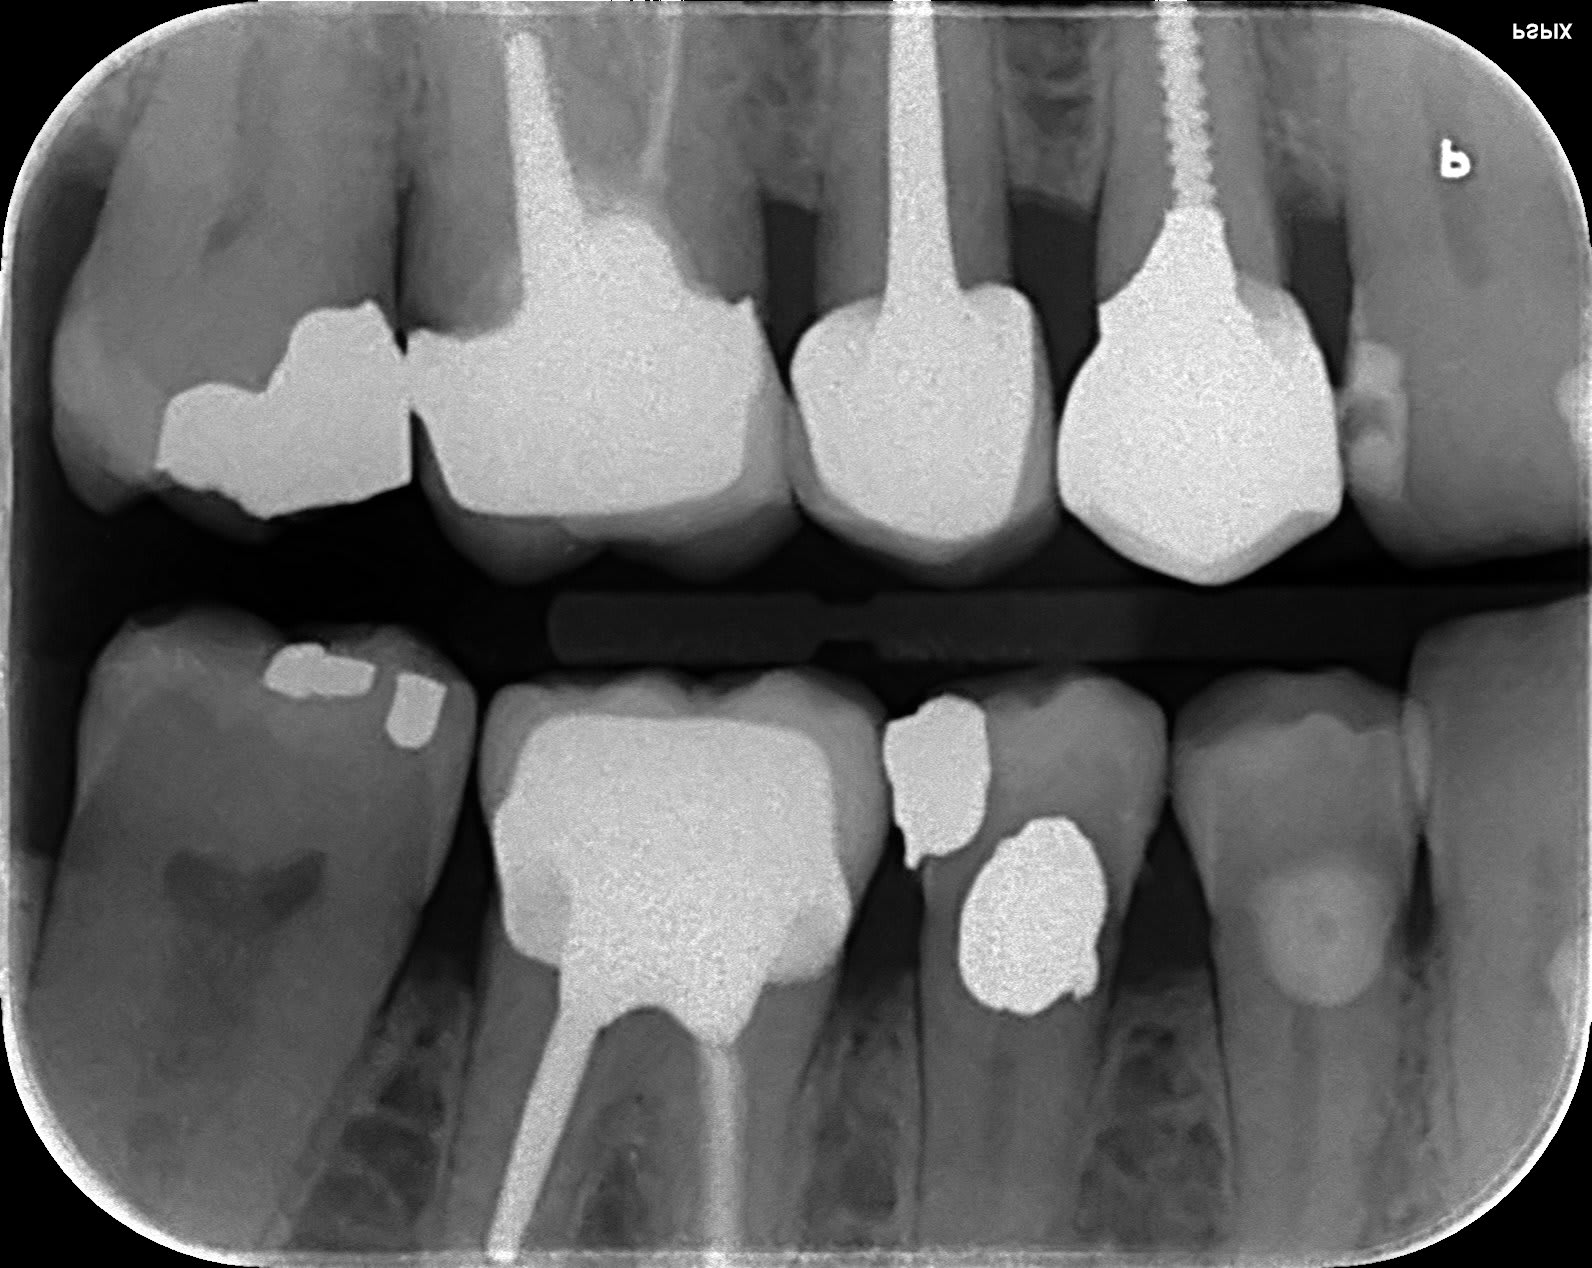

Et j'offre un minitel a celui qui trouve avec quoi je vais sauver cette petite malheureuse 🐁

Sans endo, la 5 c'est un amalgame.

Avant "reconstitutions".

non, pas de vis ni de screw post ni pivot ou autres truc pointu ou pas

voilà c'est fini ... et je vous assure que ça va tenir 10 ans au moins.... enfin si tout se passe normalement et que la patiente ne décède pas avant